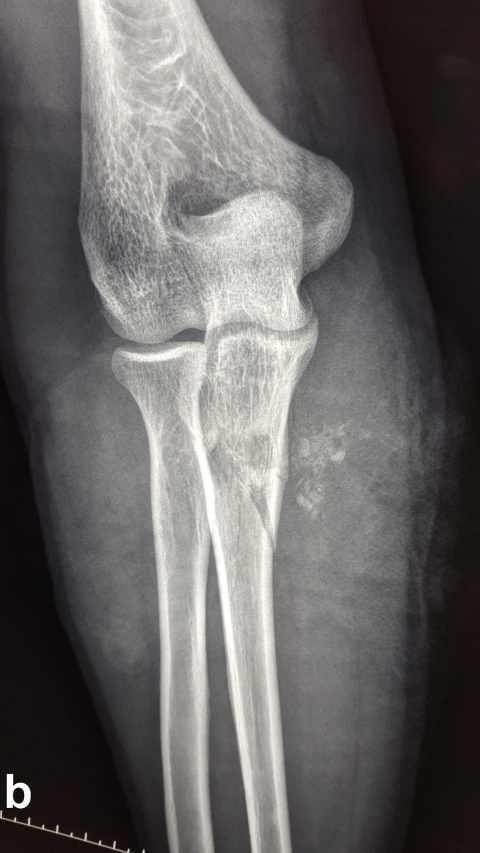

Es zeigt sich das typische Bild einer Schussfraktur nach Niedrigenergieverletzung. a seitlicher Strahlengang,

b a. p. Strahlengang

Beim Auftreffen des Projektils im Rahmen von Niedrigenergieverletzungen auf Knochengewebe entsteht meist eine typische, einfache Fraktur (Abbildung 2). Hochenergieverletzungen des Knochens münden in eine multifragmentäre Situation, bei der ein Großteil der Projektilenergie an den Knochen abgegeben wird. Insbesondere lange Röhrenknochen können, da sie wie eine starre, spröde flüssigkeitsgefüllte Röhre agieren, durch Projektile mit hoher Energie explosionsartig zerstört werden (Abbildung. 3).